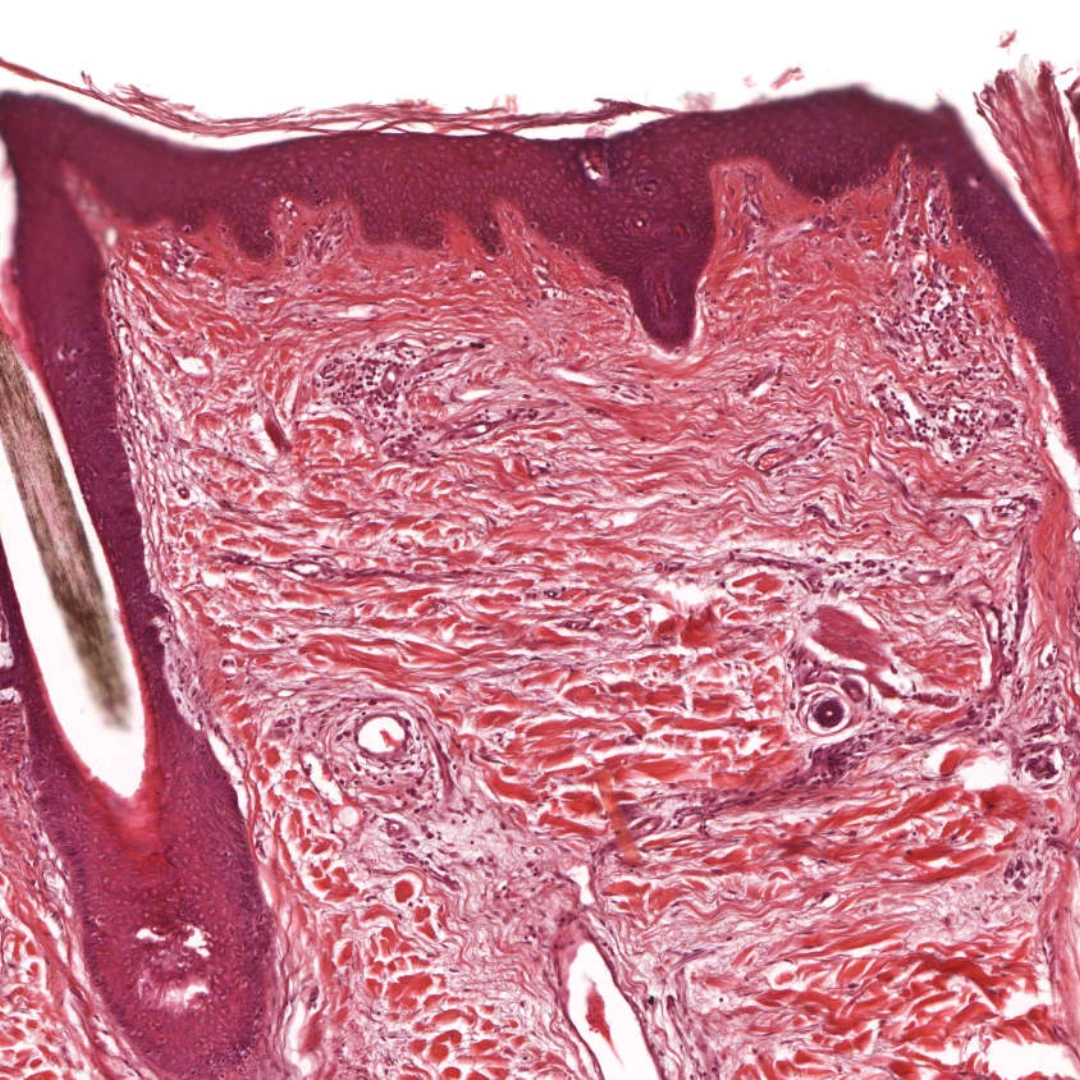

Histopathological Examination of Skin Biopsy

The Histopathological Examination of Skin Biopsy is a diagnostic test in which a small sample of skin tissue is removed and examined under a microscope. The biopsy is studied by a pathologist to assess the cellular and structural changes in the skin. This test helps identify a wide range of skin conditions, including infections, inflammatory diseases, autoimmune disorders, and cancers such as melanoma or squamous cell carcinoma.